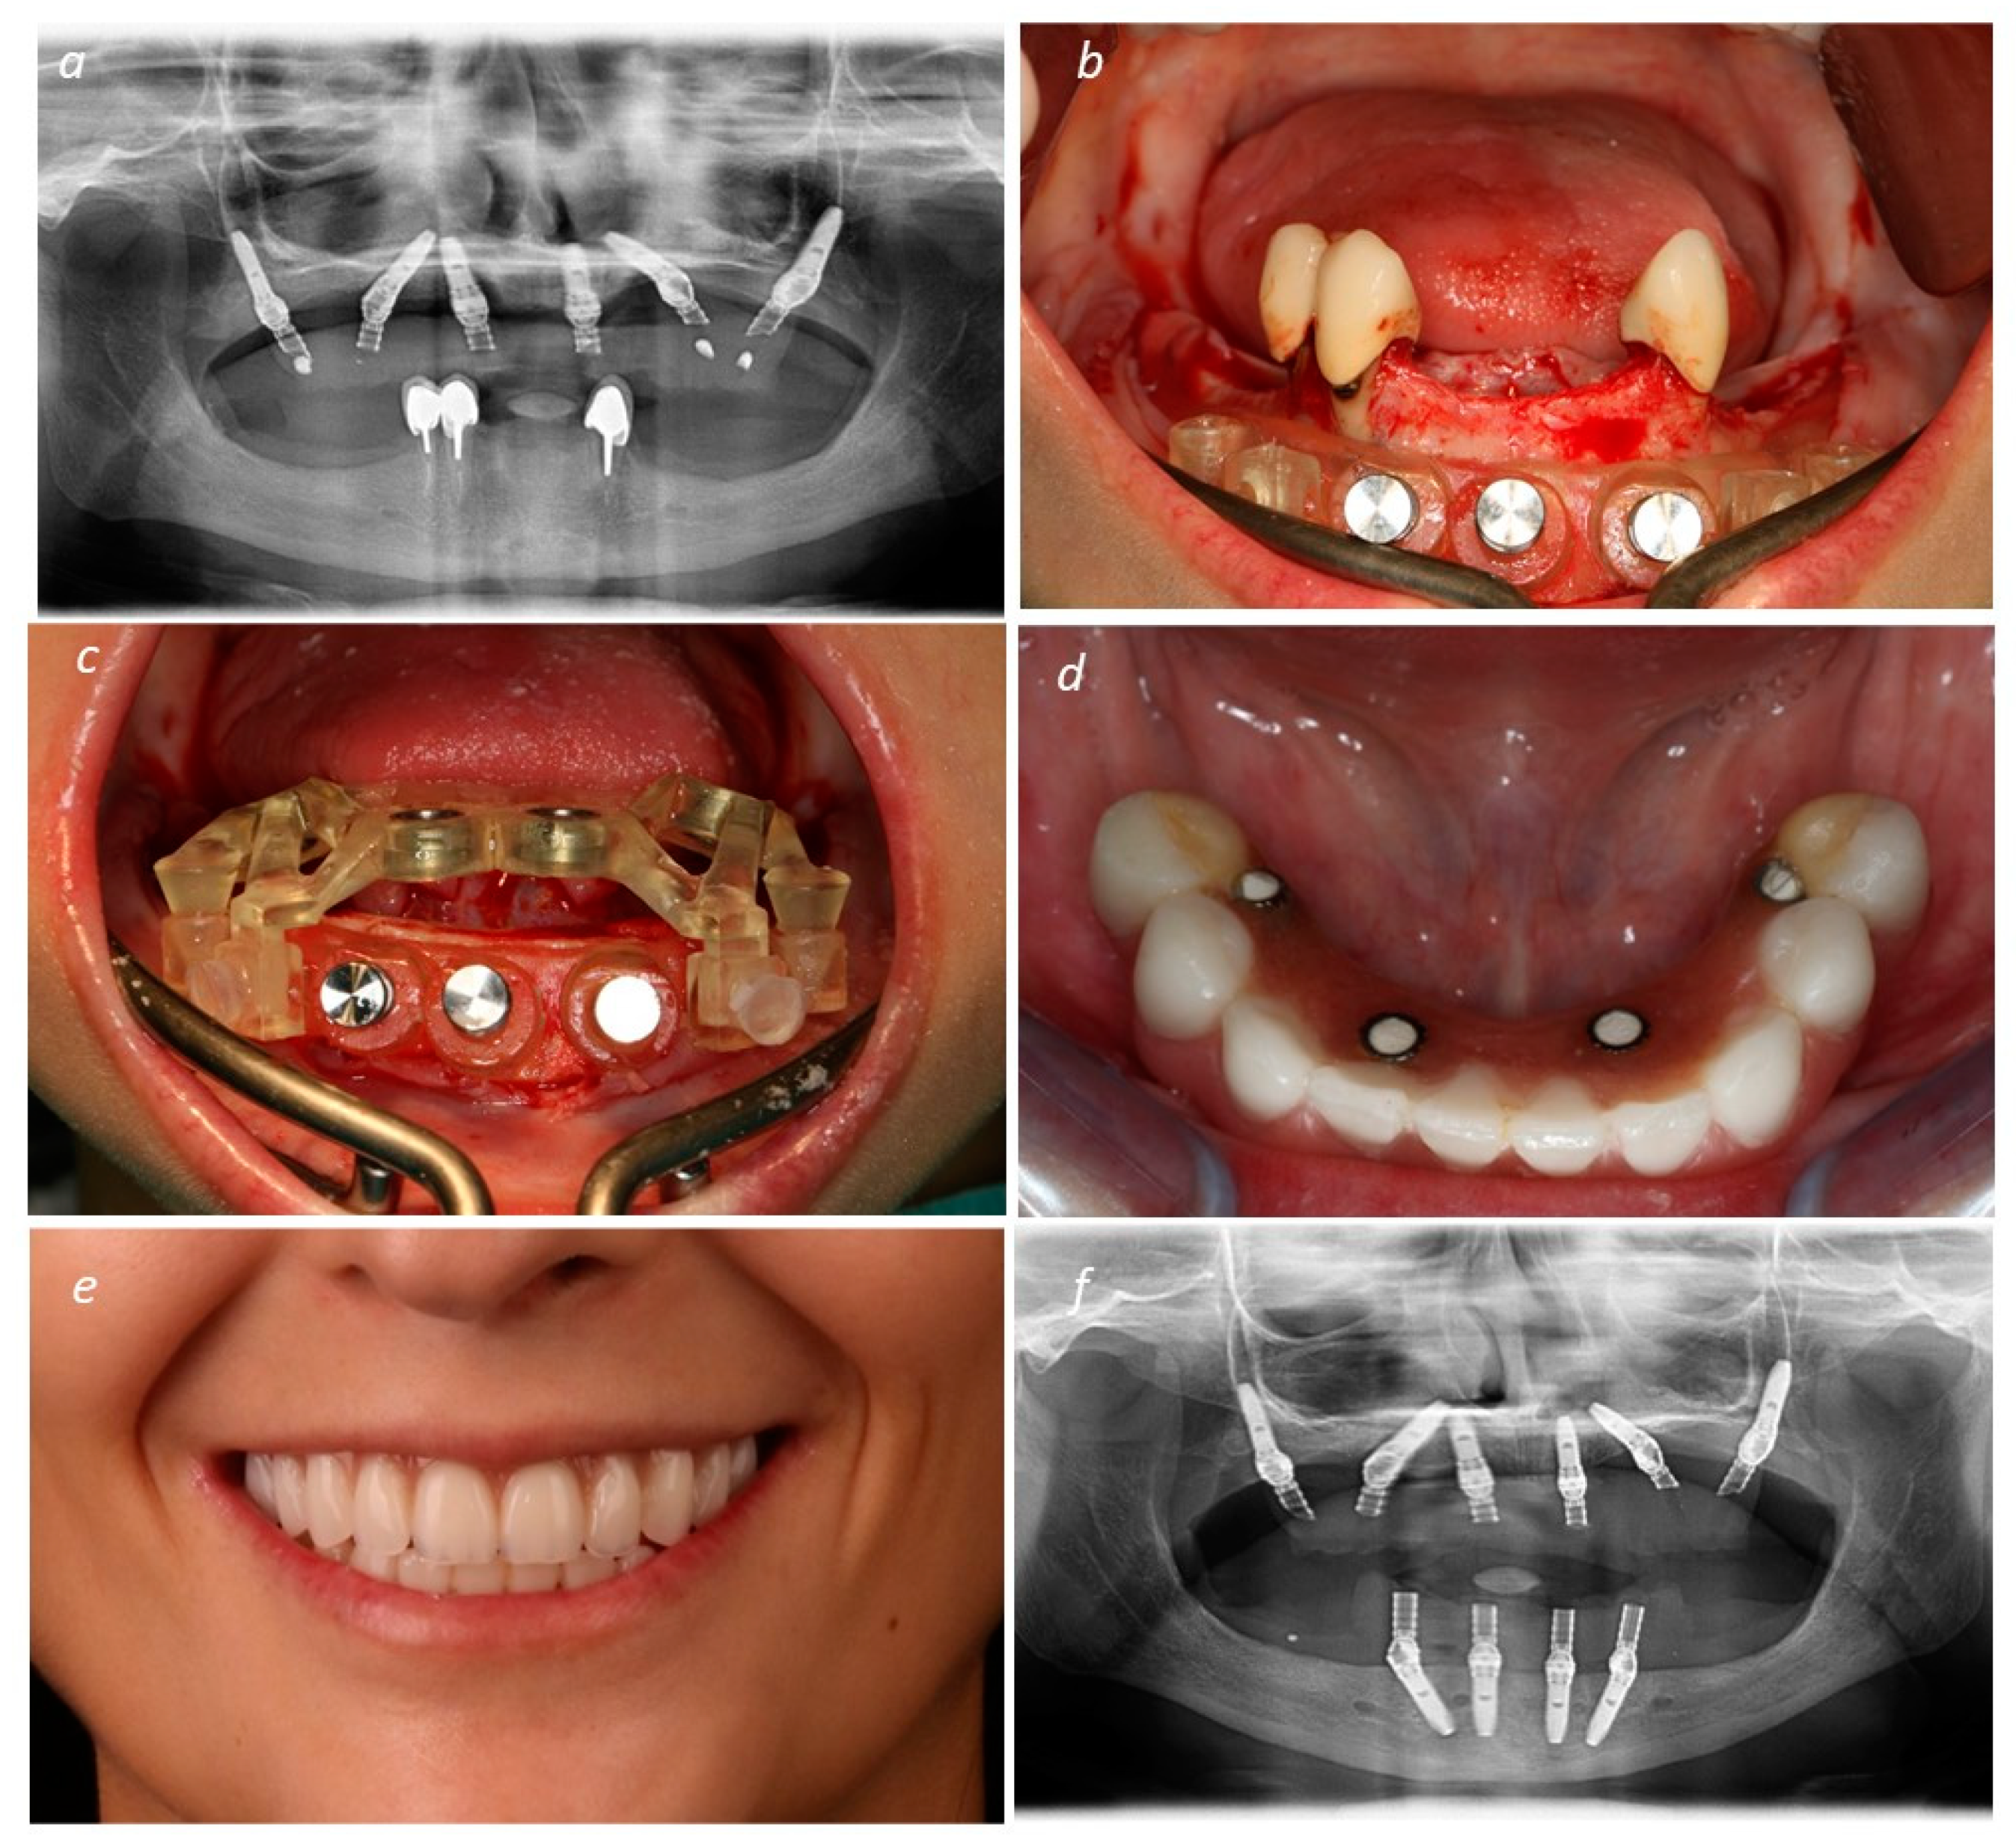

Description of the Technique